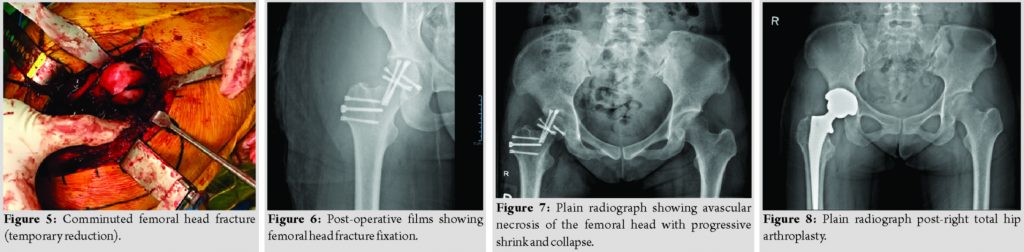

A 35-year-old female who was training for a downhill running race was running at high-speed down a hill when she tripped over a log of wood and fell forward. She subsequently complained of severe pain in her right hip and was unable to mobilize. When brought to the local hospital, plain radiograph showed a right posterior hip dislocation associated with a femoral head fracture (Fig. 1). Manipulation and reduction (M and R) were attempted, approximately within 6 h to injury, to relocate the right hip and subsequent post M and R radiographs showed iatrogenic fracture of the femoral neck (Fig. 2). She was subsequently transferred to our center for further care. On arrival, it was 48 h from the time of her injury. An urgent computed tomographic scan was done which showed a fracture-dislocation of the right hip (Fig. 3). She underwent an open surgical dislocation of the hip and internal fixation of the femoral head that same day.

As per a standard Ganz’s osteotomy [6], with the patient placed in a lateral position and through Hardinge approach, we performed a trochanteric osteotomy flipping the osteotomized trochanteric fragment anteriorly. Ganz’s osteotomy was preferred as it allowed for full exposure of the femoral head conferring advantages in fracture reduction [6] and compared to the anterior and posterior approach had the lowest risk of avascular necrosis [4]. This approach allowed for Z-shaped anterosuperior capsulotomy to dislocate the femoral head for visualization and fixation of the fracture. The fracture line ran inferior to the fovea separating a main superior and grossly comminuted inferior fragment (Fig. 4 and 5). The largest femoral head fragment was fixed to the femoral neck with two 6.5mm Depuy Synthes (Depuy Synthes, Warsaw, IN) headless compression screws and the remaining femoral head fragments were reconstructed using4.5mm headless compression screws. The femoral head was then reduced within the acetabulum and the trochanteric flip osteotomy was fixed usingheadless and cortical screws (Fig. 6). Post-operative X-rays of the hip demonstrated good reduction of the femoral head and neck fracture. Rehabilitation was started immediately after surgery. She was kept on non-weight-bearing of the operated limb for 6 weeks with gradual increase in weight-bearing thereafter with eventual full weight-bearing status at 3 months post-surgery. Four months after surgery, the patient complained of persistent right hip pain with ambulation and was unable to wean off her crutches. Plain radiographs showed avascular necrosis of the femoral head with progressive shrink and collapse (Fig.7), resulting in prominent compression screws abutting against the acetabulum. Given the clinical picture, we counseled the patient for the removal of implants and conversion to the right total hip arthroplasty (Fig.8).The patient underwent surgery uneventfully. Rehabilitation was started immediately in the post-operative period. At 12 months following surgery, plain radiographs were satisfactory and the patient could ambulate freely without pain.